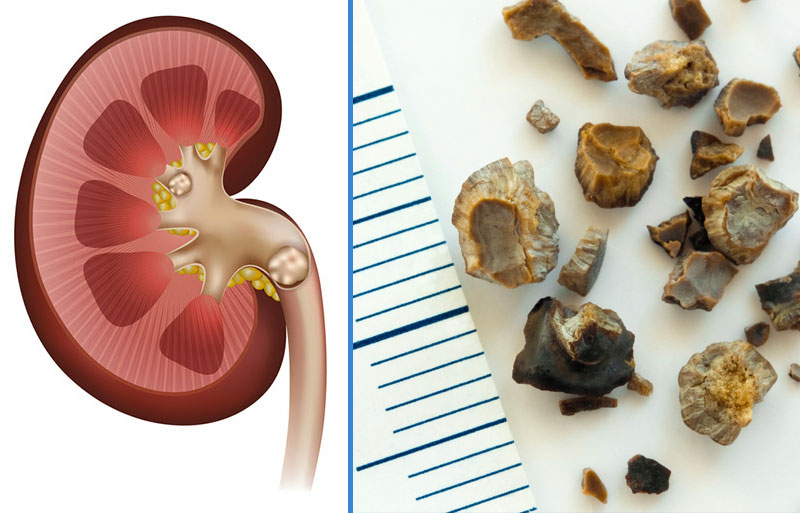

Urolithiasis is a disease characterized by the formation of urinary stones (uroliths) in the organs of the urinary system or along the urinary tract, influenced by species-specific predispositions. The term urolithiasis broadly refers to stones located anywhere within the urinary tract. These uroliths can form in the kidneys, ureters, urinary bladder, or urethra.

The most common uroliths in cats and dogs are struvite and calcium oxalate. Uroliths composed of ammonium urate and cystine are less frequently observed.

- Nephroliths: May cause sublumbar pain and hematuria, but clinical signs are often absent until the stones reach the ureter. Renal stones are typically left untreated unless ureteral obstruction occurs, with supportive care provided.

- Cystoliths: Can lead to hematuria, stranguria, and lower urinary tract inflammation. Some large stones may be palpated as thickening or friction along the bladder wall; however, the presence, number, size, and location of uroliths are usually determined by radiography or ultrasonography. The probable mineral composition can be estimated based on clinical data including age, breed, sex, urine pH, and urine bacterial culture. Definitive mineral composition is only determined through quantitative analysis of the stones.